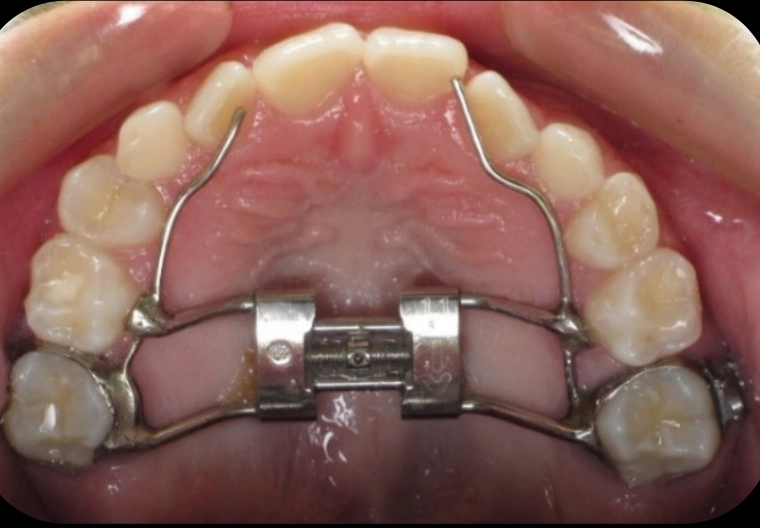

Patient treated with EXPANSION and braces

Before

After